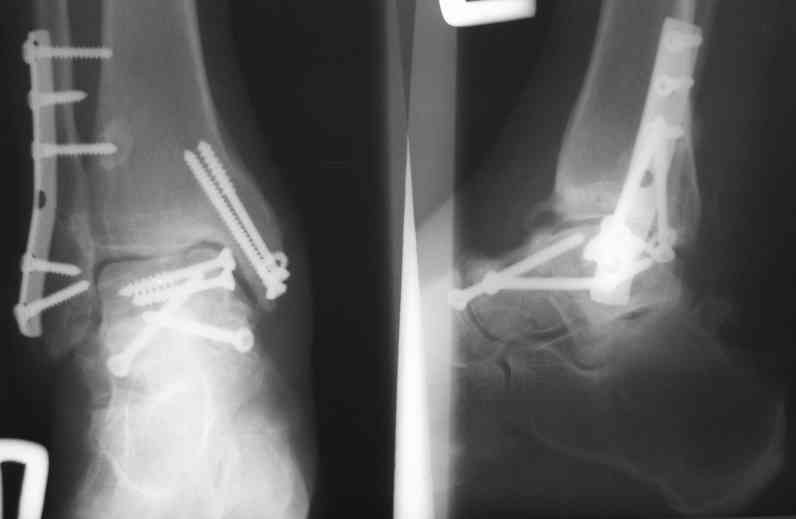

И второй случай из недавней ташкентской практики, (извините за качество ренгенограммы и только в одной проекции) случай падения с высоты (кстати моего друга - известного киноактера) - открытый

смещенный перелом тарана, с переломом переднего края дистального эпиметафиза большеберцовой кости.

При поступлении в приемной сделана первичная обработка с ушиванием открытой латеральной раны и вытяжением за пятку.

Из-за отсутствия времени пришлось оперировать на второе утро, из материала, что имеем на месте, фиксирован двумя шурупами, а третий-это контур сломанного жойстика в 4 мм. На дистальный медиальный конец тибиа antiglide 3.5 мм пластина. Через пару дней выписан и несмотря на предупреждение, самостоятельно начал нагрузку в 4 недели, время не ждет, снимается в боевике в Росийской Федерации.